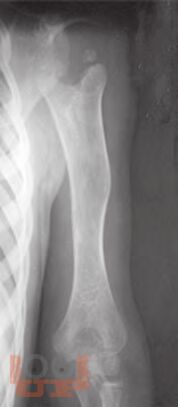

Ортопедические последствия гематогенного остеомиелита верхних конечностей у детей

Авторами представлен многолетний опыт лечения детей с ортопедическими последствиями гематогенного остеомиелита верхних конечностей. На основании комплексного обследования пациентов предложены оптимальные способы лечения детей с данной патологией.